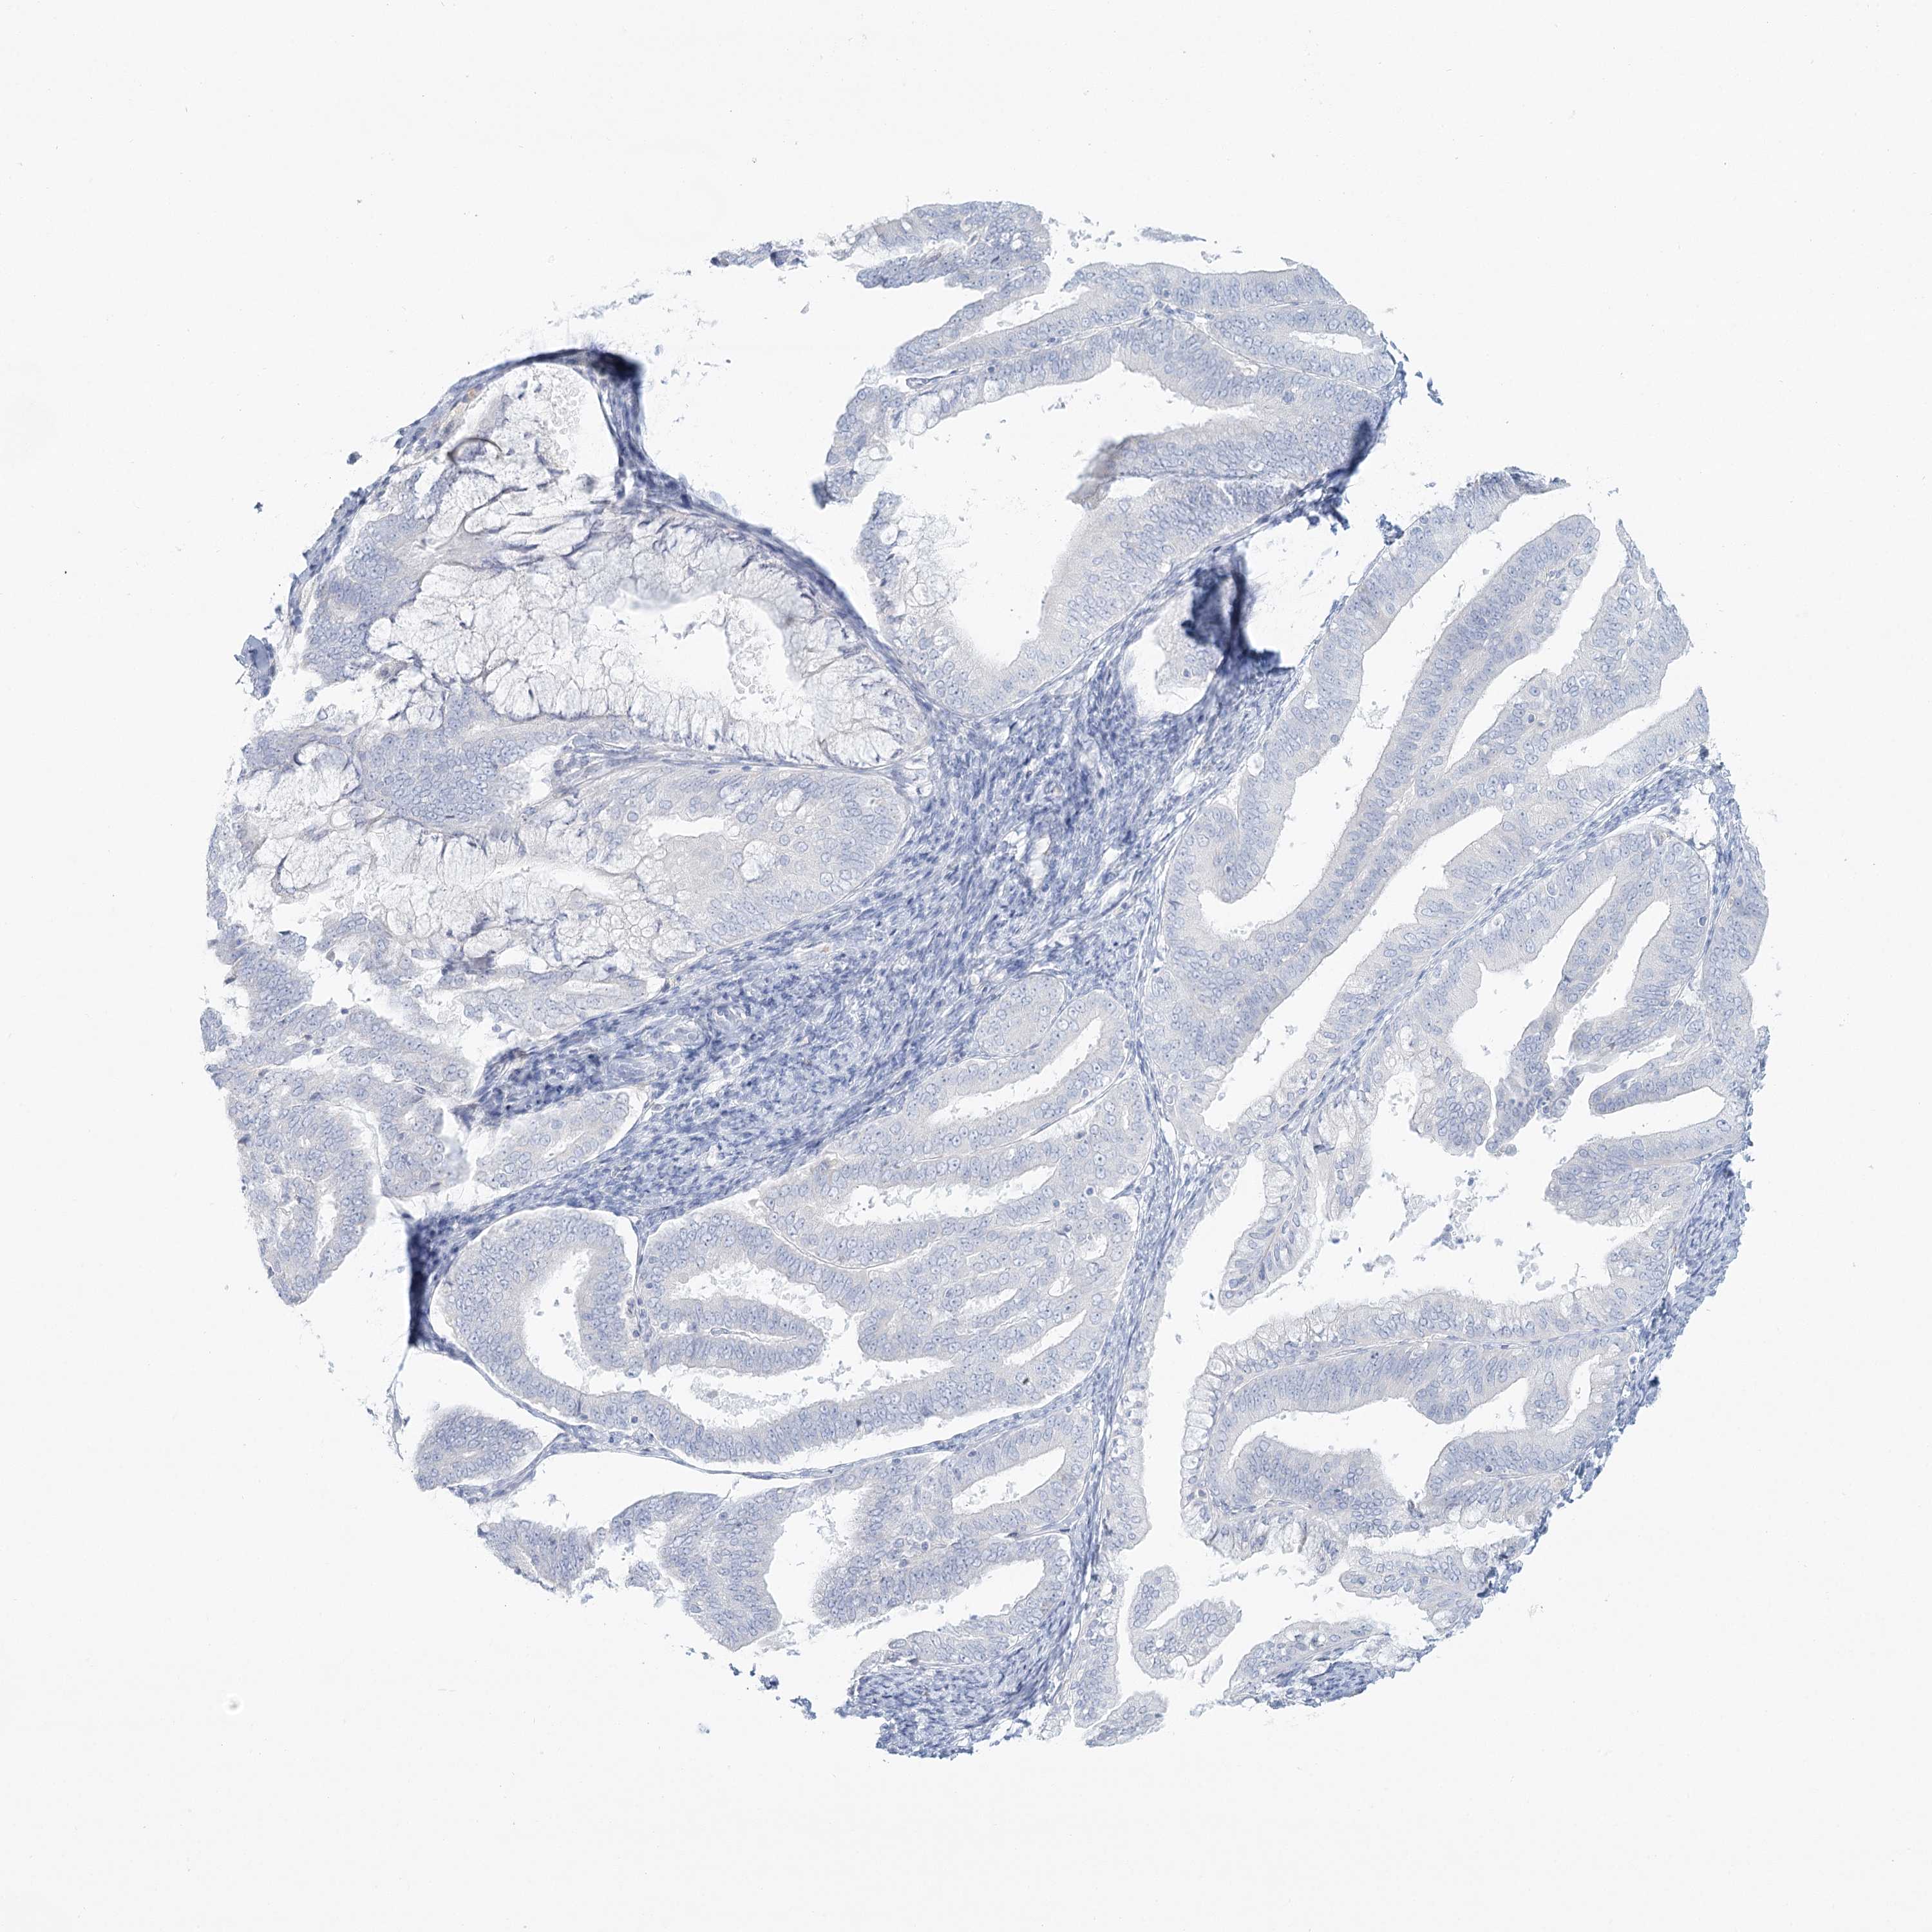

ENDOMETRIAL CANCER - Protein expressioni

A mouse-over function shows sample information and annotation data. Click on an image to view it in a full screen mode. Samples can be filtered based on level of antibody staining by selecting one or several of the following categories: high, medium, low and not detected. The assay and annotation is described here.

Note that samples used for immunohistochemistry by the Human Protein Atlas do not correspond to samples in the TCGA dataset.

Antibody stainingi

Antibody staining in the annotated cell types in the current human tissue is reported as not detected, low, medium, or high, based on conventional immunohistochemistry profiling in selected tissues. This score is based on the combination of the staining intensity and fraction of stained cells.

Each image is clickable and will lead to virtual microscopy that enables deeper exploration of all samples and also displays staining intensity scores, fraction scores and subcellular localization as well as patient and tissue information for each sample.

Antibody HPA036441

Antibody HPA036442

Staining

High

Medium

Low

Not detected

Intensity

Strong

Moderate

Weak

Negative

Quantity

>75%

75%-25%

<25%

None

Location

Nuclear

Cytoplasmic/membranous

Cytoplasmic/membranous,nuclear

Adenocarcinoma, NOS

Adenoma, NOS